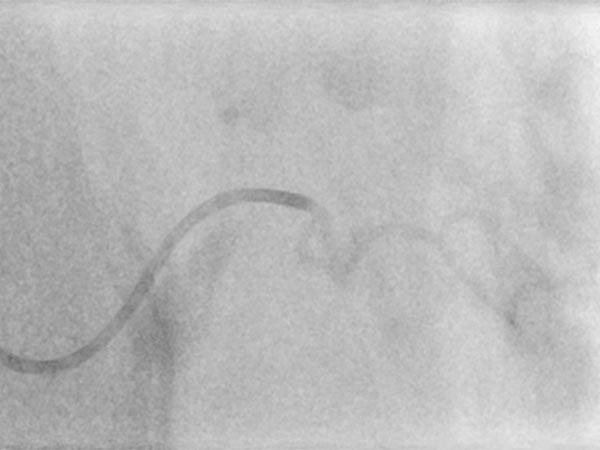

As there was still no tendency to regression of the tumor at the end of the 3rd year, embolization was performed after biopsy to induce involution. Digital subtraction angiography (DSA) shows a microcatheter superselectively introduced into a tumor vessel. The tumor is heavily perfused and lobulated, very early venous outflow, typical of an NICH.

Particle embolization with spherical particles 250 micrometers in size via the microcatheter inserted superselectively into the tumor.

More tumor vessels with blush-like diffuse enhancement, typical of a vascular tumor / NICH. All these vessels must be selectively embolized to induce involution.

Further selective particle embolization. The embolization particles mixed with contrast medium remain in the tumor vessels.

Overview angiography via the left external iliac artery also shows no remaining perfusion of the tumor anymore, thus the tumor vascularization is successfully and superselectively completely occluded. All non-pathological arteries are preserved.